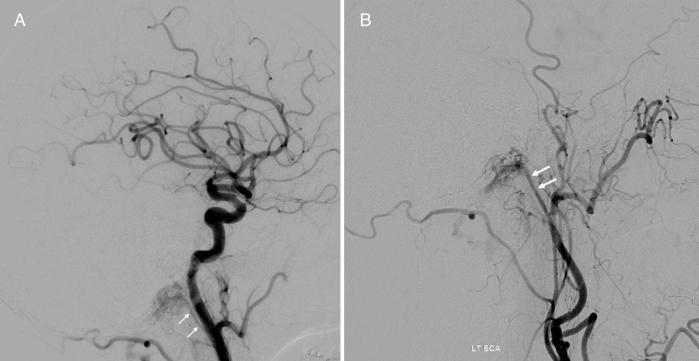

The authors describe the case of HCDAVF in a 74-year-old male who presented with pulsatile tinnitus (PT) lasting 3 months and significant fatigue, headaches, and dizziness. Diagnostic cerebral angiography demonstrated a left-sided HCDAVF with bilateral supply from the ascending pharyngeal arteries and fistulous connection at the level of the left anterior condylar vein (ACV). This lesion was consistent with a Cognard and Borden type I dAVF.

作者描述了一名74岁男性HCDAVF病例,该患者出现搏动性耳鸣(PT)持续3个月,伴有明显疲劳、头痛和头晕。诊断性脑血管造影显示左侧HCDAVF,由咽升动脉双侧供血,瘘口位于左侧前髁静脉(ACV)水平。该病变符合Cognard和Borden I型dAVF。